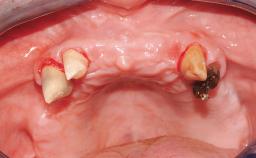

Immediate Loading of Four Implants in the Mandible and Final Restoration with a Full-Arch Metal Framework FDP

A fully edentulous 65-year-old woman was referred to our clinic for esthetic and functional dental rehabilitation. The patient presented with inadequate complete maxillary and mandibular prostheses, insufficient vertical dimension, and extensive tooth wear. The clinical examination and anamnesis showed no local or systemic contraindications, no signs or symptoms of bruxism, and an absence of smoking habits. The treatment proposed was implant placement in the mandibular interforaminal area and immediate loading with a fixed definitive prosthesis. A removable mucosa-supported complete prosthesis was indicated for the upper jaw, since its bone structure offered satisfactory retention and the financial condition of the patient disfavored a full-mouth implant-supported rehabilitation.

# of Implants 4

Type of Implants One-Piece